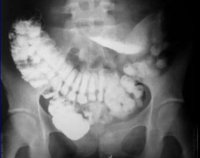

Рентгенограмма кишечника с усилением контраста является наиболее информативным методом выявления висцероптоза. Контраст раскрывает выпадение кишечника, расширение некоторых его отделов. Используя задержанные изображения, проверьте скорость прохождения через кишечник.